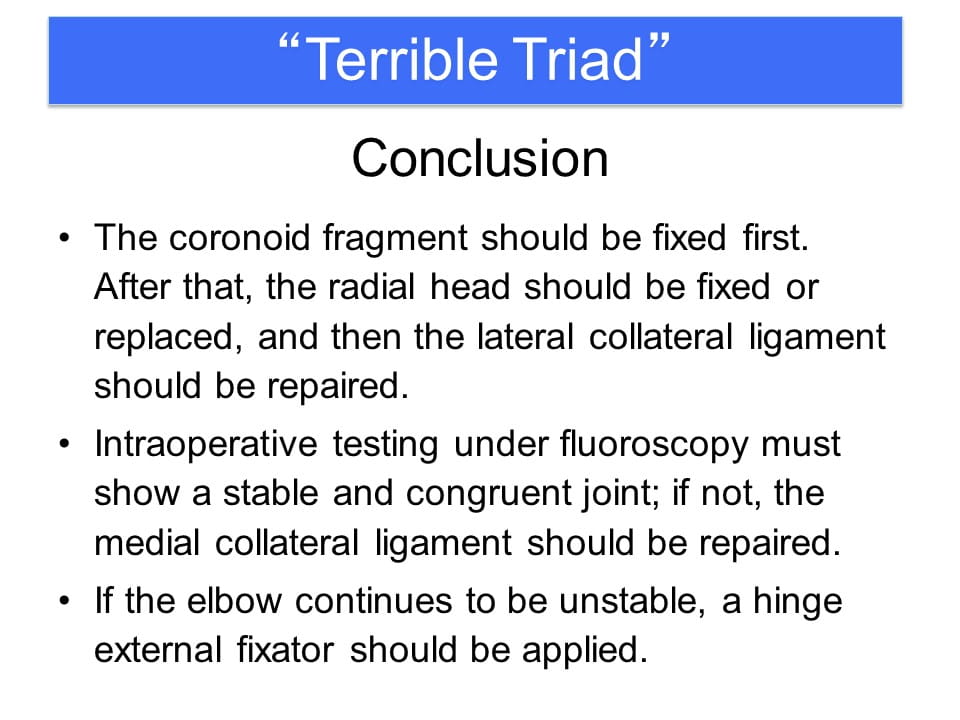

Terrible Triad